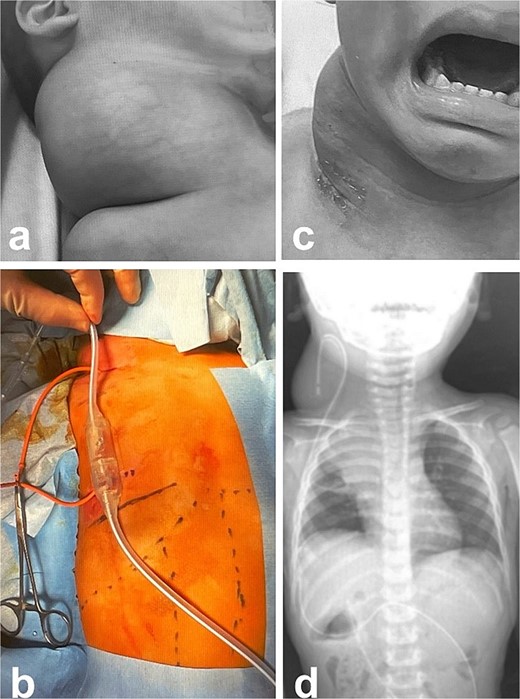

MRI findings after removal of the Denver shunt catheter. (a) MRI findings showed two different areas of intensity in the neck region and the mediastinal region where the Denver shunt was inserted. (b) MRI findings 2 months postoperatively showed that the mediastinal lesion was smaller with near-complete regression. (c) X-ray showed no tumor shadow and no compression of the trachea by the lymphangioma. (d) MRA showed disappearance of the lymphangioma. (e) and (f) Right cervical swelling did not become evident, even when crying (e: crying, f: smiling).

A male infant weighing 2726 g was born at 38 weeks of gestation. Antepartum ultrasonography and magnetic resonance imaging (MRI) revealed a right cervical cyst, suggestive of a lymphangioma. A right cervical cyst was noted at birth and gradually decreased in size thereafter. However, right cervical swelling became evident when he cried (Fig. 1a and b). An MRI obtained at 21 months of age showed a huge cyst in the right cervical mediastinal region. Following diagnosis of a lymphangioma with hemorrhage, he was treated with Eppikajutsuto®, a Japanese traditional Kampo medication, 2 g/d (0.2 g/kg). An MRI revealed tumor enlargement after oral administration of Eppikajutsuto® for 2 months. A complex vascular malformation was noted (Fig. 2) and the dose was increased to 5 g/day (0.5 g/kg). A repeat MRI 2 months after the dose increase showed no reduction in the size of the tumor. After another 4 months, the dose of Eppikajutsuto® was further increased to 7.5 g/d (0.65 g/kg). The tumor in the cervical region had enlarged further with an accompanying risk of airway system compression (Fig. 3a–c). A puncture and suction of the lymphangioma was performed for volume reduction and the content was prepared for bacterial culture. The content was dark red in color, which was consistent with hemorrhage. The white blood cell count (WBC) was 19 190/μl and the C-reactive protein (CRP) concentration was 5.77 mg/dl. He was admitted to the hospital to undergo treatment with intravenous and oral antibiotics. The bacterial culture results were negative. On the 22nd day of hospitalization, the WBC count was 8780/μl and the CRP concentration was 0.39 mg/dl. On the 24th day of hospitalization, a Denver shunt was inserted from the right cervical region to the abdominal cavity to reduce the volume of the cervical cyst to prevent airway obstruction (Fig. 4a–c). A pump chamber with a backflow prevention valve was implanted in the right anterior chest subcutaneous tissue (Fig. 4b). By applying pressure to the chamber, the cyst fluid in the neck was returned to the abdominal cavity. The patient was discharged on the 6th post-operative day. The swelling in the right neck was reduced and the pressure on the trachea was relieved based on the X-ray findings (Fig. 4c and d). On the 5th day after hospital discharge, the patient was febrile and the right neck swelling recurred. A hemogram revealed severe anemia and bleeding within the neck cyst was suspected. He was readmitted to the hospital and on the 2nd day after admission the cervical cyst was punctured, which yielded bloody contents. A transfusion was performed for anemia secondary to hemorrhage in the neck cyst. Sirolimus (1 mg), a mammalian target of rapamycin inhibitor, was added 7 months after starting Eppikajutsuto® due to a concern that administration of a Kampo medication and insertion of the Denver shunt might not be effective. An X-ray showed that the tip of the catheter may have moved within the cyst, which caused the catheter tip to penetrate the cyst and resulted in bleeding within the neck cyst (Fig. 5a). Serial MRI findings showed that the old bleeding site was within the mediastinal region of the lymphangioma. Revision surgery was performed 3 weeks after inserting the Denver shunt. Intraoperative findings showed that the tip of the catheter had penetrated the cyst wall (Fig. 5c). There were cyst walls with a septum on the mediastinal side of the cyst and when incised old bleeding was noted and the walls were opened as much as possible (Fig. 5d). The tip of the catheter was rounded and fixed with threads. The catheter was returned to the cyst and the wound was closed (Fig. 5b). The patient was discharged 9 days after the 2nd surgery. The concentration of sirolimus on the 14th day of administration was 9.9 ng/mL (normal range: 5–15 ng/ml). On the 16th day after the second hospital discharge, the neck had enlarged, the surgical wound was erythematous, and discharge was noted at the site of the pump chamber. Bacterial cultures of the punctured the neck cyst content and the wound discharge grew Staphylococcus aureus. On the 24th day after the 2nd hospital discharge, the blood concentration of sirolimus 1 month after starting oral administration was 19.7 ng/ml. Therefore, the oral administration of sirolimus was temporarily discontinued. At the same time the patient developed a high fever and the 3rd operation was performed to remove the Denver shunt due to a catheter infection. The blood concentration of sirolimus 6 days after discontinuation was 1.4 ng/ml. An MRI on the 6th post-operative day from the 3rd operation revealed two different intensities in the neck and mediastinal regions where the Denver shunt was inserted (Fig. 6a). On the 10th day after the 3rd operation, the patient was discharged from the hospital but laboratory testing showed an elevated WBC count (13 250/μl) and CRP concentration (6.03 mg/dl). Three months after the 3rd hospital discharge, the right neck swelling abruptly decreased in size and the WBC count and the CRP concentration decreased to the normal range. An MRI 2 months after the 3rd operation showed that the mediastinal lesion was smaller with near-complete regression (Fig. 6b). The neck swelling was minimal 6 months after the 3rd operation. An X-ray showed no tumor shadow and no compression of the trachea by the lymphangioma (Fig. 6c) and magnetic resonance angiography (MRA) showed that the lymphangioma had regressed (Fig. 6d). Currently, no right cervical swelling is evident when the patient cries (Fig. 6e and f) and he is doing well with oral administration of Eppikajutsuto® (7.5 g/d [0.65 g/kg]).